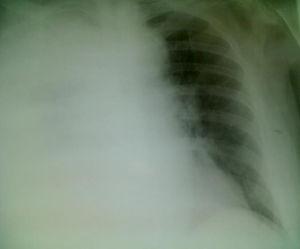

Varón de 57 años de edad, fumador de 15 cigarrillos/día, sin hábito enólico ni otras drogodependencias. Como único antecedente patológico de interés presenta trastorno obsesivo-compulsivo en tratamiento con sertralina 100mg/24h. Acude a nuestra consulta por fiebre alta (40°C), escalofríos y artromialgias de 3 días de evolución, que no mejoran con paracetamol 1g/6h. En la exploración física destacan: afectación del estado general, presión arterial de 97/63mmHg, frecuencia cardíaca de 90 pulsaciones/min, frecuencia respiratoria de 20 respiraciones/min, saturación de O2 del 94%, temperatura de 39,2°C, auscultación cardiopulmonar normal, exploración abdominal anodina —salvo leve molestia a la puño-percusión lumbar izquierda— y exploración neurológica sin signos meníngeos ni focalidades. Se deriva a urgencias del hospital de referencia para valoración etiológica del cuadro clínico dada la afectación del estado general, la baja saturación de O2 y la no mejoría de la fiebre con antitérmicos. En la analítica se aprecia: leucocitos, 15,44×109/L (91% neutrófilos y 3% linfocitos); velocidad de sedimentación globular, 96mm/h; proteína C reactiva, 382mg/L; procalcitonina, 2ng/mL; tasa de protrombina, 58%; INR, 1,36; tiempo de tromboplastina parcial activada, 34s; fibrinógeno, 6,35mg/L; siendo el sedimento urinario normal. La antigenuria de neumococo es negativa, pero la de legionela es positiva. El electrocardiograma y la ecografía reno-vésico-prostática resultan normales. La radiografía de tórax muestra condensación en el lóbulo superior derecho (fig. 1). Se cursan hemo, copro y urinocultivos, cultivo de esputo incluyendo bacilo de Koch y serologías (virus hepatitis A, B y C, VIH, lúes, citomegalovirus, virus Epstein-Barr, fiebre tifoidea, Campylobacter, herpesvirus, neumococo, micoplasma y legionela), que son inicialmente negativas 2 semanas después producirse seroconversión para L. pneumophila serogrupo 1. Durante su estancia en urgencias inicia distress respiratorio e hipotensión arterial severa, ingresando en unidad de cuidados intensivos (UCI) con cobertura antibiótica a base de levofloxacino y claritromicina intravenosos, monitorización hemodinámica y respiratoria, intubación orotraqueal y ventilación mecánica y nutrición parenteral periférica. En UCI se hace una radiografía de tórax con portátil apreciándose afectación pulmonar con derrame pleural derecho total (fig. 2). Tras buena evolución clínica, a los 7 días se procede a la extubación y se ingresa en planta de medicina interna para control y seguimiento del paciente quien, tras 5 días, permanece asintomático y con radiografía de tórax de control normal.